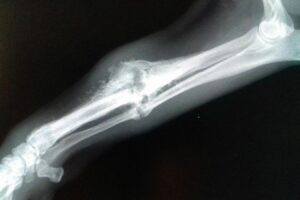

Im Rahmen der Kastration wurde auch Ricardas rechtes Vorderbein geröntgt. Die italienischen Tierärzte möchten nicht mehr daran rühren, aber wir lassen die Röntgenaufnahmen noch in Deutschland von einem Spezialisten für Orthopädie begutachten und hoffen, dass der lieben Hündin doch noch geholfen werden kann!